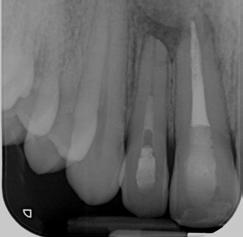

Then, the medicament was changed to calcium hydroxide, which was changed every 12-15 weeks. After 6 months, a periapical surgical procedure was performed in order to remove the broken instrument from the apical area of tooth 12 while tooth 11’s root canal was filled with GP cones and Ah-26 cement. Upon patient’s request, internal whitening was also done for his tooth 11, followed by a composite filling 1 week later.

Radiograph 2 Radiograph 3 Radiograph 4

2. After root filling tooth 11 (30/03/2023)

3. Immediately after surgical removal of the broken file (30/03/2023)